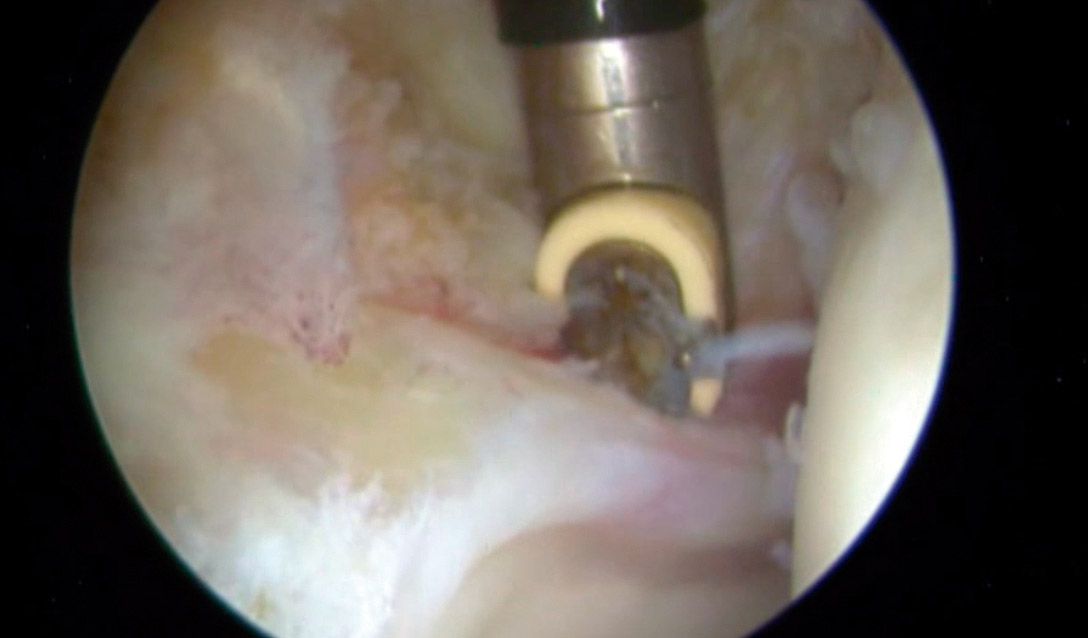

En vista de su evolución, se decidió realizar una cirugía artroscópica de cadera derecha bajo la sospecha de AFA sin signos radiológicos. La imagen artroscópica mostraba un labrum hiperémico con una zona anterosuperior con rotura condrolabral y lesiones cartilaginosas acetabulares de tipo ALAD 1 con wave sign presente (Figura 7). Se realizó una sinovectomía local con vaporizador de radiofrecuencia y reanclaje labral mediante sutura.